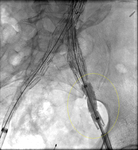

Resolución de la endofuga tipo I, resuelta con la expansión de la extensión

University of Michigan, específicamente los casos del Dr. Upchurch que reflejan los Departamentos de Cirugía Vascular y Radiología